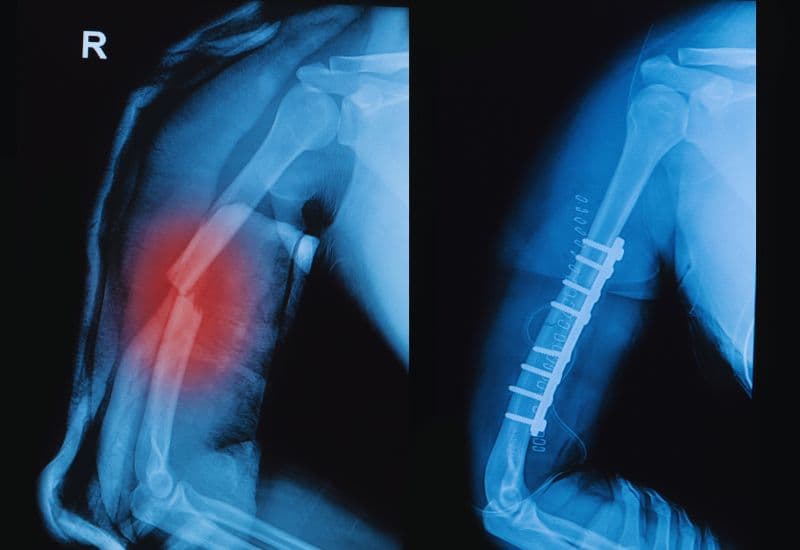

4.2 Phẫu thuật gãy xương cánh tay

Trong trường hợp chấn thương gãy cánh tay nghiêm trọng, đặc biệt là khi xương bị gãy thành nhiều mảnh hoặc có di lệch nghiêm trọng, phẫu thuật là phương pháp điều trị hiệu quả nhất. Bác sĩ sẽ tiến hành mổ đặt lại các mảnh xương gãy, có thể sử dụng đinh hoặc nẹp vít để cố định xương lại. Phẫu thuật giúp xương được phục hồi nhanh chóng và giúp bệnh nhân tránh được các biến chứng như mất chức năng cánh tay.